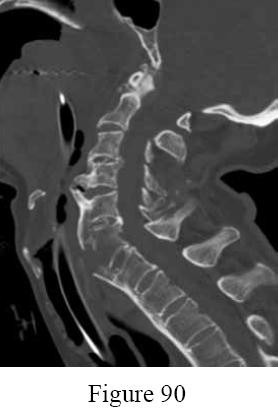

Figures A and B are pre-operative and intra-operative radiographs of a 67-year-old male that has undergone a left total hip arthroplasty under general anesthesia. The patient had no motor deficits preoperatively. During the operation, the trial acetabular and femoral components were positioned and reduced with no complication. Intraoperative leg lengths were equal. Before implanting the real components, the surgeon and anaesthesiologist performed a wake up test, which revealed that the patient was unable to dorsiflex the left foot. What would be the most appropriate next step in the management of this patient?

This patient has undergone a left THA with significant leg lengthening. The biggest concern is stretch to the sciatic nerve. The most appropriate step at this stage would be to perform a subtrochanteric osteotomy to decrease leg length and sciatic nerve stretch.

Patients with DDH that have undergone a large limb-lengthening procedure are at a greater risk due to the significant stretch of the sciatic nerve. Intraoperative procedures that have been shown to prevent this outcome include good pre-operative planning, limb lengthening